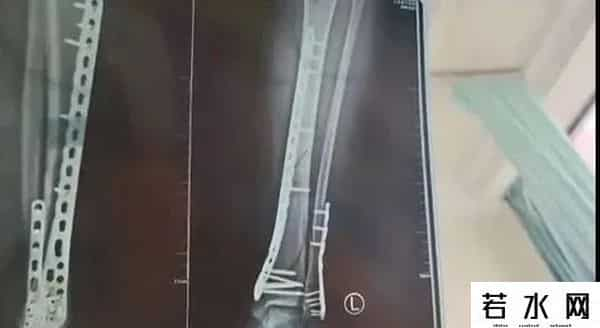

甘肃兰州武女士称

2024年母亲节当天

她穿着7厘米厚的洞洞鞋下楼

不慎崴脚摔倒

致使自己左腿粉碎性骨折